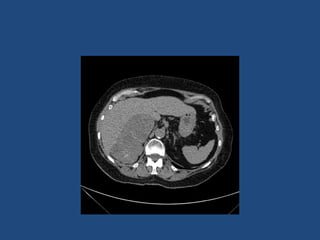

Imaging

• CT better at eliminating malignancy

(dedicated CT looking at Hounsfield units (HU)

and washout characteristics)

– <10HU = benign (sens 71%, spec 100%)

• MRI may characterise phaeos better

• FDG-PET good for phaeos and cancer

• FNA – consider if cancer history and >10HU on CT

after exclusion of phaeo

Imaging - size

• >4cm 90% sensitivity carcinomas

24% specificity (ie only 24% cancer)

• >6cm 25% chance of it being carcinoma

• <2cm + hypodense then unlikely to grow

• If change in size >1cm over 6 months consider

resection

Imaging • CT betterat eliminating malignancy (dedicated CT looking at Hounsfield units (HU) and washout characteristics) – <10HU = benign (sens 71%, spec 100%) • MRI may characterise phaeos better • FDG-PET good for phaeos and cancer • FNA – consider if cancer history and >10HU on CT after exclusion of phaeo

Imaging - size •>4cm 90% sensitivity carcinomas 24% specificity (ie only 24% cancer) • >6cm 25% chance of it being carcinoma • <2cm + hypodense then unlikely to grow • If change in size >1cm over 6 months consider resection • Guidelines suggest: – NIH: 2 CTs 6M apart – Young et al + UptoDate: 0,6,12,24m – BES: Repeat image – increase in size of 0.8cm over 6-12M consider surgery